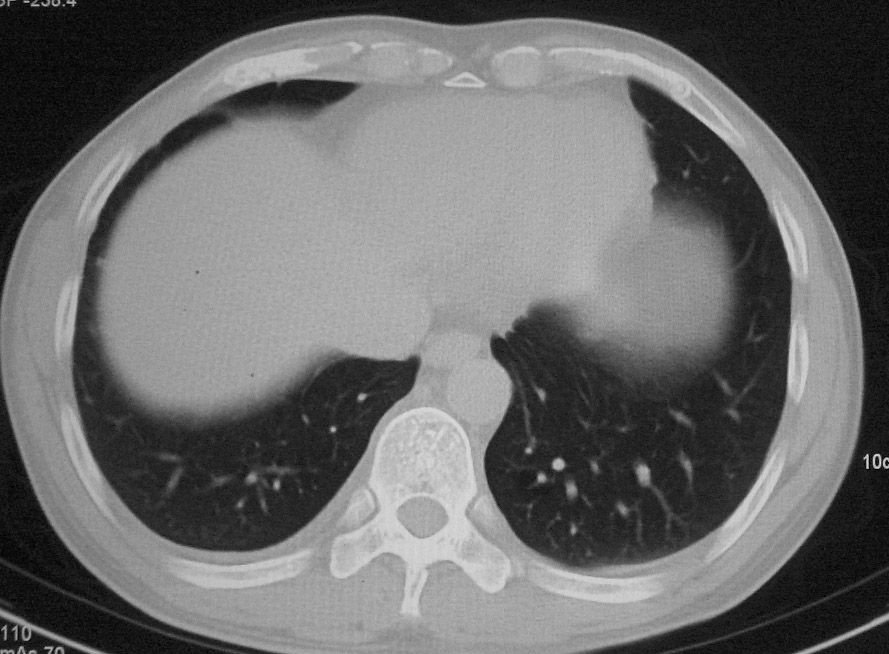

左肺上叶不张,左肺上叶支气管狭窄,呈鼠尾征,左侧胸腔内见少许积液,考虑左肺上叶中心型肺伴左侧胸腔内少许积液可能,不除外结核,建议支气管镜检查.

右肺上叶中央型肺癌并上叶肺不张、纵隔淋巴结肿大

右上叶支气管后壁明显增厚,支持右肺上叶中央型肺癌伴右上叶肺不张、纵隔淋巴结肿大。

左肺上叶不张,可见软组织肿块,左肺上叶支气管狭窄,呈鼠尾征,左侧胸腔内见少许积液,纵隔内未见肿大淋巴结,建义做个增强或支气管镜

右上叶支气管后壁明显增厚,支持右肺上叶中央型肺癌伴右上叶肺不张、纵隔淋巴结肿大。建议支气管镜检查。

右上肺中央性肺癌伴右侧胸腔少量积液!右上肺胸膜下还有一小病灶,不完全排除结核,但个人支持恶性肿瘤!建议早穿刺活检。

右上叶支气管开口变窄,纵隔见肿大的淋巴结。支持右上叶中心型肺癌并右上叶不张纵隔淋巴结肿大。

右肺上叶中央型肺癌并上叶肺不张、纵隔淋巴结肿大.右侧少量胸腔积液。

右上肺中心型肺癌并肺不张,纵膈淋巴结肿大。右侧少量胸腔积液。

右肺上叶支气管后壁增厚,呈鼠尾状狭窄,纵隔内未见明显增大的淋巴结影,考虑为中央型肺癌伴右上肺不张